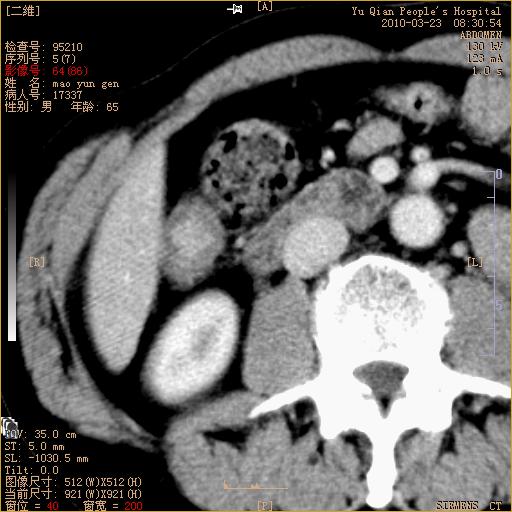

标题: CT25266:消瘦月余,前来肝部检查,请看看肠腔 [打印本页]

标题: CT25266:消瘦月余,前来肝部检查,请看看肠腔

升结肠肠壁增厚,不均强化,考虑升结肠腺癌可能性,建议肠镜检查。

1)考虑升结肠癌。2)右肾小囊肿。